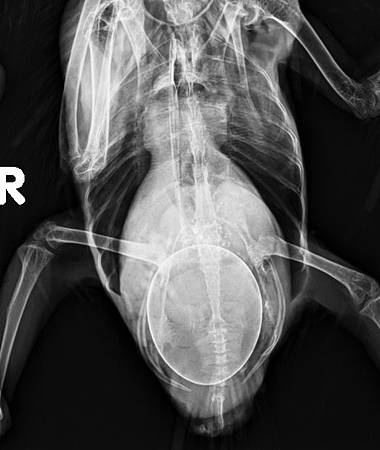

蛋size過大的問題屬於急症需要及早診斷,因為超過骨盆的大小就會無法自然產出,需要開刀或是從泄殖腔夾碎取出。如果蛋已經下行至輸卵管末端,從泄殖腔可視之位置,就可以使用此法將蛋夾碎後取出